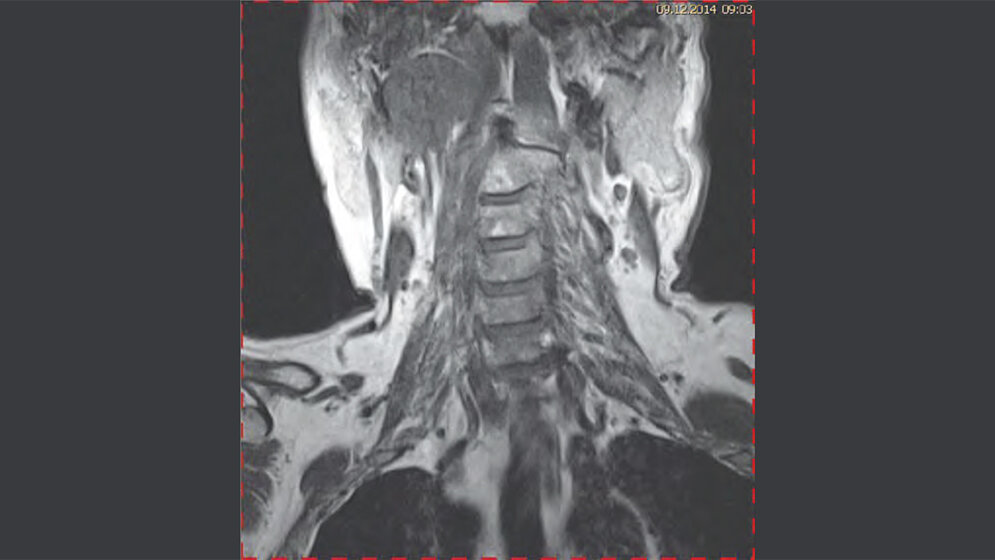

Zufallsbefunde: Laterale Halszyste

Die Halszysten sind kongenitale Anomalien, verursacht durch Überbleibsel der Kiemenbogengänge. Sie stellen etwa 30% aller Anomalien des Halsbereiches dar. Viele der Halszysten sind asymptomatisch. Ultraschall, Computertomographie und Kernspintomographie werden zum Nachweis eingesetzt und um im Falle einer Infektion oder Größenwachstum die chirurgische Behandlung zu planen.